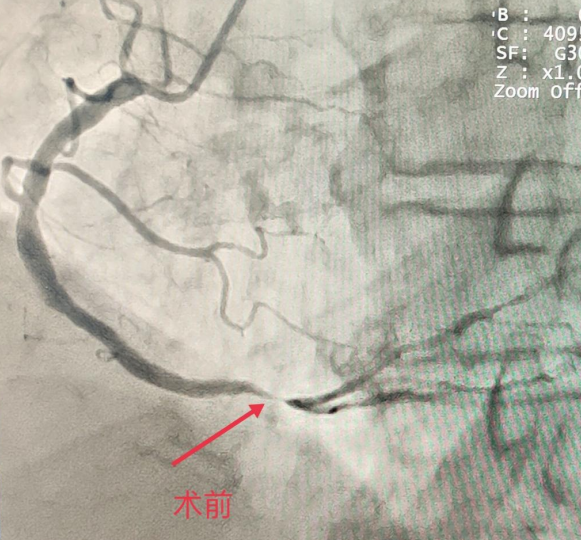

患者官某,89岁,男性,胸痛6小时入院,经检查,诊断为“急性下壁ST段抬高心肌梗死”,需进行冠状动脉造影检查+支架植入手术。在征得患者及家属同意后,经皮行桡动脉血管穿刺后,通过心导管到达心脏冠状动脉进行冠状动脉造影检查和支架植入手术,成功开通血管后患者胸痛消失,安返病房。经心内科医护人员的精心治疗与护理,患者病情平稳,生命体征正常,得到了患者及家属的认可。

此例冠脉造影+支架植入术的顺利完成,填补了威远县人民医院在心脏病微创治疗方面的空白。